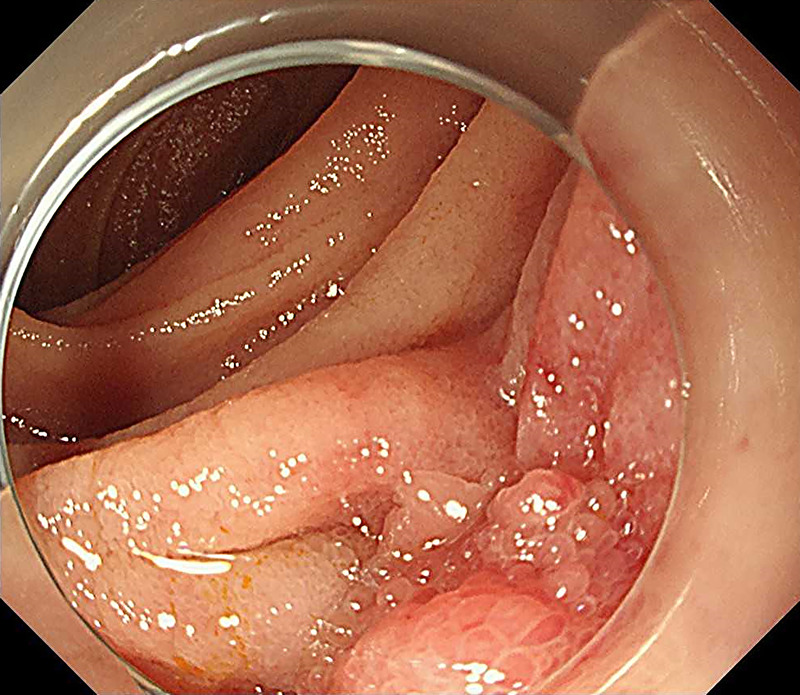

Successful EUS-guided fine-needle biopsy using a forward-viewing echoendoscope for local recurrence at the choledochojejunal anastomotic site 13 years after pancreaticoduodenectomy for cholangiocarcinoma.

胰十二指肠切除术治疗胆管癌13年后胆肠吻合口局部复发,超声引导下前视超声内镜下细针活检成功。